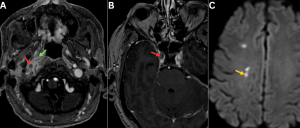

Fig 11: Clinical history:

A 55-year-old diabetic male presented with facial numbness, visual blurring, and acute-onset gait imbalance.

Figures A–C:

Axial diffusion-weighted imaging (DWI), apparent diffusion coefficient (ADC), and FLAIR images demonstrate diffusion restriction with corresponding T2/FLAIR hyperintensity involving the right trigeminal nerve (red arrows), consistent with trigeminal neuritis. Additionally, acute infarcts are noted in the right cerebellar hemisphere, showing DWI hyperintensity with corresponding ADC hypointensity and FLAIR hyperintensity (green arrows).

Figures D–F:

Axial DWI, ADC, and FLAIR images demonstrate diffusion restriction with associated T2/FLAIR hyperintensity involving the right optic nerve (white arrows), consistent with optic neuritis.